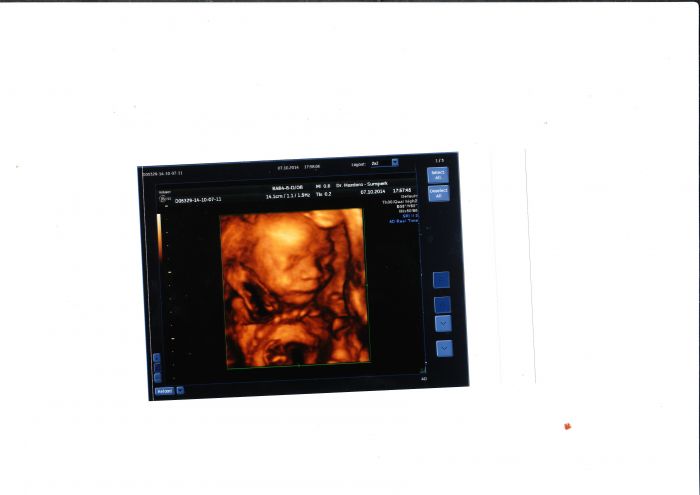

Brozanko máš krásné fotečky

a na té druhé jak si spokojeně spinká.